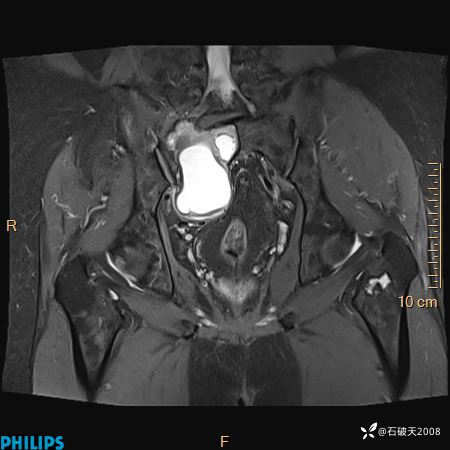

2023年3月份MRI影像

T2压脂冠状位